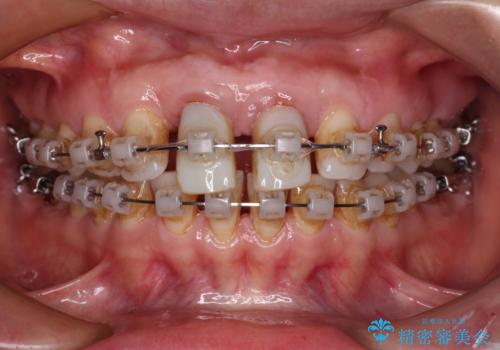

- 矯正装置

- クリアブラケット

- 治療期間

- 2年6ヶ月

- 治療回数

- 30回以上